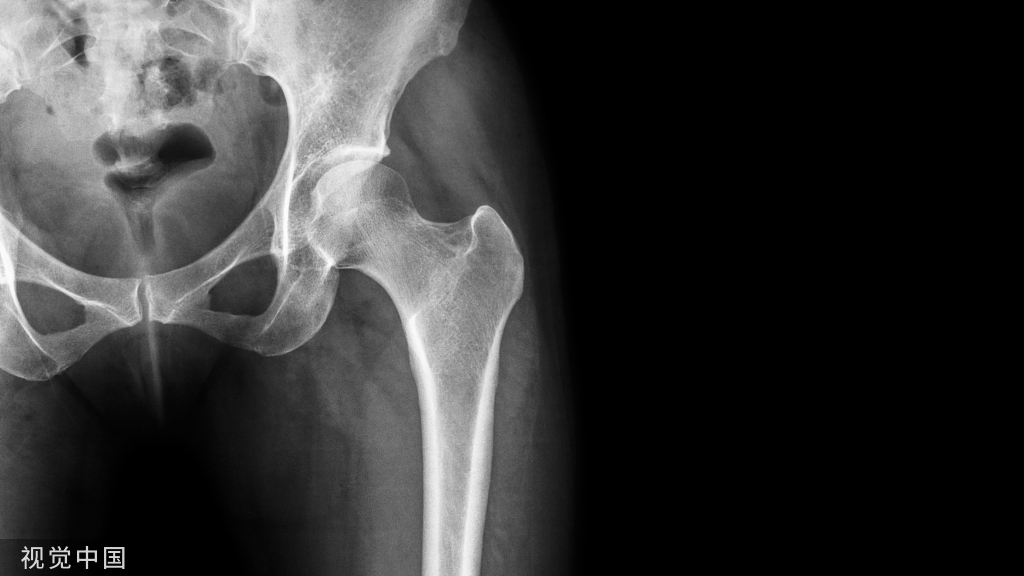

MIS-TLIF(minimally invasive transforaminal lumbar interbody fusion,微创经椎间孔入路腰椎椎间融合)作为脊柱外科通道技术和腰椎经典融合手术TLIF(transforaminal lumbar interbody fusion,经椎间孔腰椎椎体间融合术)的结合体可完成椎间孔摘除髓核+微创经皮内固定

图:TLIF和MIS-TLIF

MIS-TLIF手术从多裂肌肌间隙进入完成,无需广泛切开肌肉韧带等软组织,具有创伤小恢复快可早期恢复活动等优势。